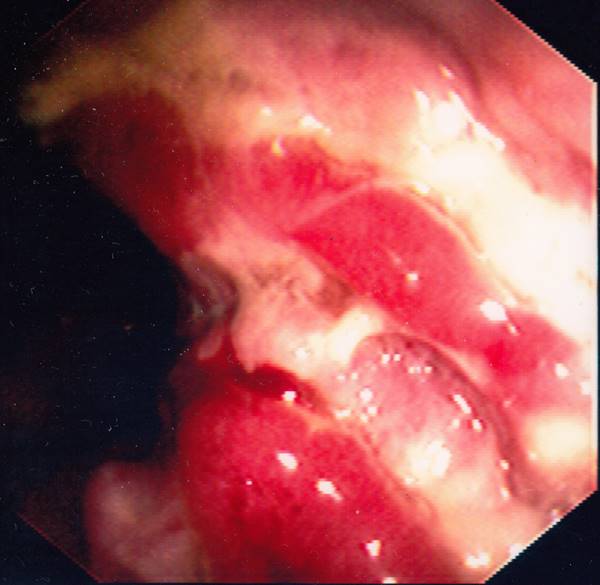

![]() Severe Rectal Crohn  |

![]() Severe Rectal Crohns Disease. Just click on a picture!  |

Severe Rectal Crohns Disease